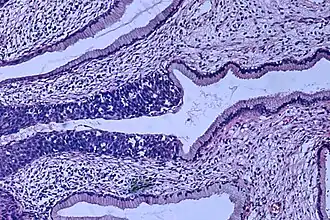

![]() Гистологическая картина аденокарциномы на ранней стадии | |

Рак ше́йки ма́тки — злокачественное новообразование в области шейки матки. Гистологически различают две его основные разновидности: аденокарцинома и плоскоклеточный рак. В настоящее время считается доказанной связь заболеваемости вирусом папилломы человека и риском развития рака шейки матки[2].